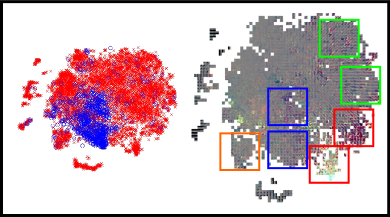

CNNs can be interpreted as models that transform the input images into a feature representation in which classes can be separated by the linear model in the last layer. The topology of such a space will depend on the ability of the deep learning features to characterize the inputs. Hence, if features are sufficiently good to differentiate each type of input, at least two well separated regions would be visually identified. Due to the high dimensionality of the feature space, a method is needed to embed multidimensional vectors in a 2D space, while preserving the pairwise distances of the points. The -distributed stochastic neighbor embedding (-SNE) was recently introduced for this purpose (Van Der Maaten, 2014). We followed this approach to study the complementarity of each characterization method, and to qualitatively assess how their integration contribute to improve their original discrimination ability. Figure 14 presents the -SNE mappings of the DIARETDB1 test samples for each characterization approach and for our combined feature vector. The CNN descriptors corresponds to those learned in Experiment 1. The figure also includes a visual representation of the organization of the patches in the embedding space. In general, it is possible to see that the ensemble approach groups the majority of the true positive candidates within a single neighboring area. By contrast, the individual characterization strategies are not able to achieve a single cluster but rather obtain two–in the case of the deep learned features–or more–using the hand crafted features.

Detailed regions of the embeddings are depicted in Figure 15. This allows better visualization of particular scenarios such as the patches around the true red lesions, the false positive candidates located in the vascular structures, the artifacts due to speckles of dirt in the lens–which are typical of the images in DIARETDB1–and the false detections within the optic disc. In general, it is possible to observe that CNN features are able to better characterize the orientation and the visual appearance of the true lesion candidates, while the hand crafted features can detect the less obvious lesions under low contrast conditions. The ability of the CNN features to discriminate orientations are more evident when dealing with vascular structures. The hand crafted approach, by contrast, is only able to capture the overall size of the vessels and their intensity properties. When combining both strategies, the main advantages of each of them are maintained. The robustness against artifacts is evident for both the deep learning based and the hand crafted features, as these false positive candidates are grouped together into separate clusters from the true lesions. A similar behavior is observed when dealing with false candidates within the optic disc area.

In general, the integration of both the deep learned and the hand crafted features significantly improved results compared to using either approach separately. In a per lesion evaluation, the combined approach achieved a consistently higher CPM value both in the e-ophtha and DIARETDB1 test sets, and also a higher per lesion sensitivity for FPI=1, which corresponds to a clinically relevant number of false positives (Niemeijer et al., 2010). These values are also higher than those obtained by two recently published baseline methods that were evaluated on the same data set. A similar behavior is observed when evaluating the method on a per image basis. The combined approach improved the performance obtained by each characterization approach separately, meaning that the integration of both sources of information obtains a better characterization of the lesion candidates and, consequently, a more accurate detection of the individual lesions. This is supported by the extensive analysis presented in Section 4.3. Despite the fact that sufficiently deep CNNs are known to be able to learn any function of arbitrary complexity, the lack of data with lesion-level annotations does not allow our network to identify the same properties that the hand crafted features do. Nevertheless, in the analysis of the -SNE mapping presented for each method (Figures 14 and 15) it is possible to see that the CNN has the ability to characterize fine-grained details such as the orientation of the lesion that are ignored by the manually selected descriptors. On the other hand, the hand crafted features have the ability to discriminate other low contrast lesions (Figure 15), specially hemorrhages (Figure 8(b)). As a result, the ensemble approach is able to outperform each individual alternative, improving performance for detecting both MA and HE simultaneously. Due to the high cost of accurately annotating small lesions, we hypothesize that this observation will continue to stand in the near future.